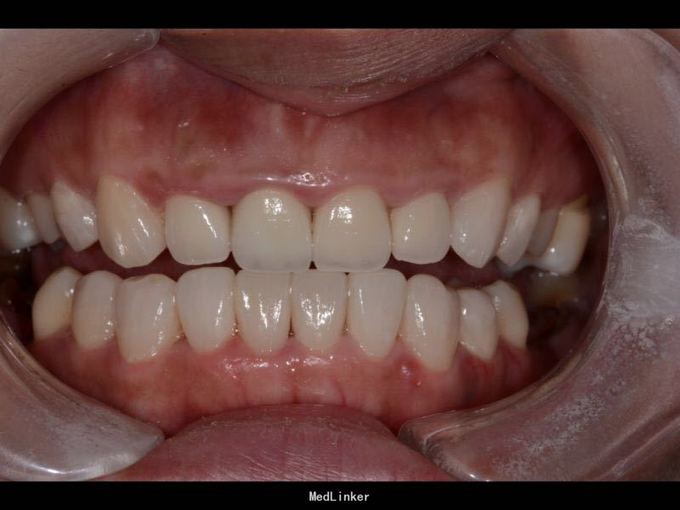

上门牙外伤金属烤瓷冠修复七年,牙龈发黑,红肿,有异味,颜色黄不美观,其他牙也黄不美观,要求重新修复

11 12 21 22死髓牙,不良修复体,牙龈炎 36 37 46 47残根 牙列不齐 处置:全口洁治。 比色,拍照,取模型做蜡型。 拆除旧修复体,拆桩核,做根管治疗,纤维桩修复,牙体预备,取模,做临时冠,粘固。11 12 21 22全瓷冠修复,13 14 23 24 31 32 33 34 41 42 43 44瓷贴面修复。

1.旧修复体覆合大,11 212 21 22龈缘位置较低且不对称,能做冠延长协调红白美学,更好 2.拆旧桩核要小心根折,用超声振动,一点一点拆.11桩核粘固比较牢固,根尖炎,定期观察行根尖手术倒充填。 3贴面的粘接,耐心